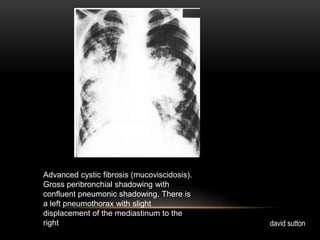

Advanced cystic fibrosis (mucoviscidosis).

Gross peribronchial shadowing with

confluent pneumonic shadowing. There is

a left pneumothorax with slight

displacement of the mediastinum to the

rightediastinum to the right david sutton